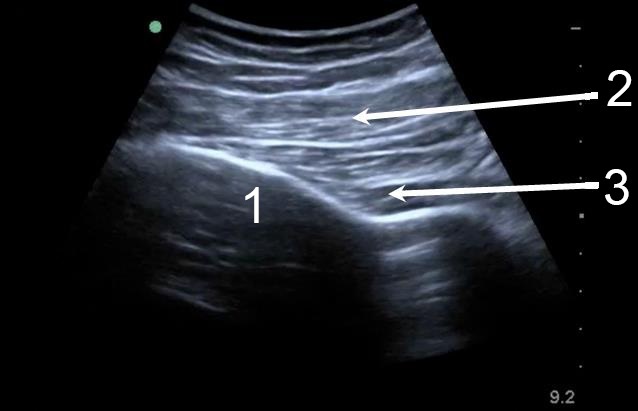

Hip Posterior Hip Soft Tissue 1 Image

Ilium

Gluteus Maximus

Gluteus Medius